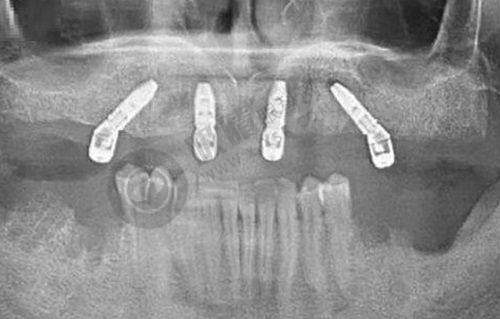

口腔诊疗服务: - 种植牙:这是该门诊部的重点项目之一,目前还有优惠活动,原价15000元起,现仅需9800元起。对于那些牙齿缺失的患者来说,是一个不错的选择。 - 牙齿矫正:帮助患者改善牙齿排列不整齐等问题,让牙齿变得更加美观和健康。 - 儿童口腔保健:专门为儿童提供口腔保健服务,培养孩子们良好的口腔卫生习惯,预防口腔疾病的发生。